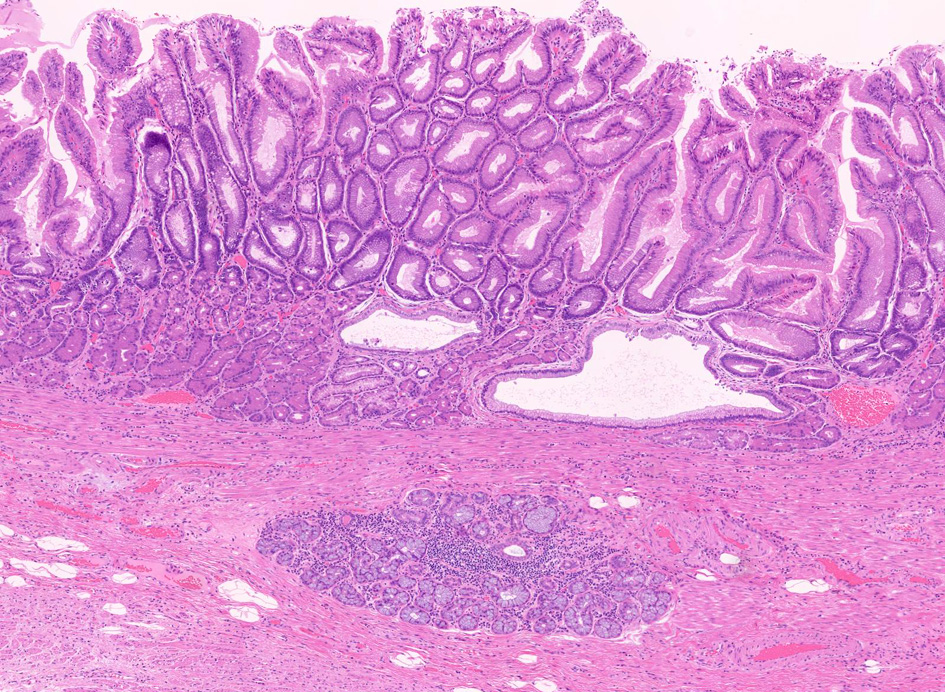

1. 固有食道腺と導管が円柱上皮部位に存在する確定診断

2. 円柱上皮下の粘膜筋板二重化:かなり確実な所見,8割はあたり

固有食道腺(Esophageal Glands Proper:EGP)とは何か

EGPは常に扁平上皮から誘導されてできる腺で, その存在は必ず一度は粘膜内に扁平上皮があったという印であり食道固有の構造である。

扁平上皮島連続切片の観察では,すべての扁平上皮島は固有食道腺と導管を介して結合している

固有食道腺の開口部は必ず扁平上皮で囲まれており, 食道腺の上皮が進展しBarrett上皮ができるとする由来説は誤りである。

Fig.1 Barrett食道 腺癌Fig.2 EGP